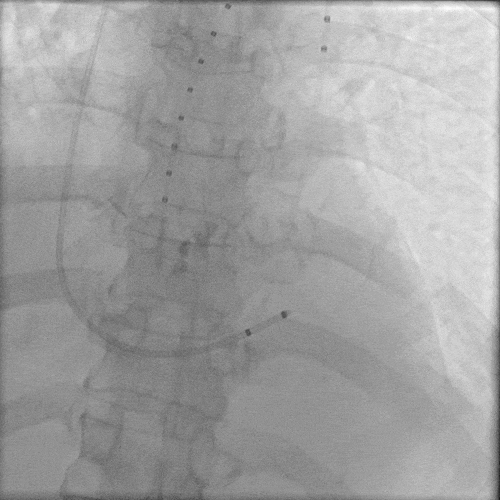

入路血管多处钙化,腹主动脉分叉前病变较重,双侧血管内径良好,整体入路血管条件尚可。

外周血管入路评估

右侧股动脉为主入路,左侧辅助入路,使用20F血管鞘。